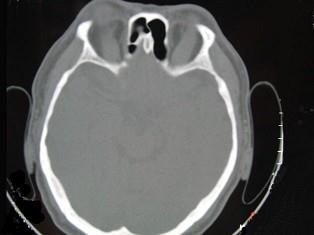

问题 女性50岁,消瘦、多饮多食,脖子粗大,双侧眼球突出,一年余,CT检查如图所示,应考虑为 ( )

选项 A、横纹肌肉瘤 B、眶部结核 C、甲状腺眼病 D、炎性假瘤 E、眼型格氏病

答案 C